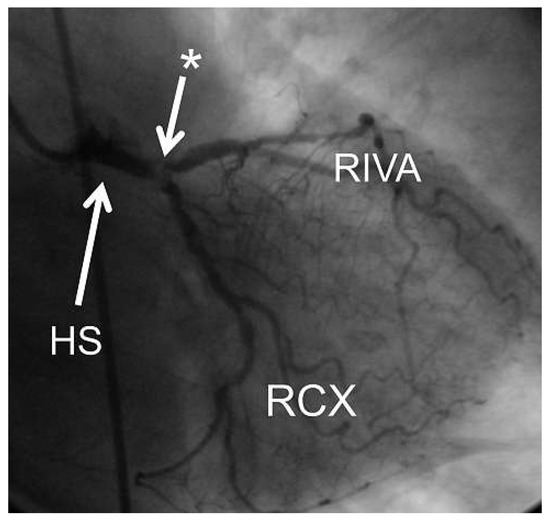

6 pages, 1978 KB

Article

Complex Percutaneous Coronary Interventions by Transradial Approach Using Sheathless Guiding Catheters

by Stephane Noble, Robert Francis Bonvini, Caroline Frangos, Pierre-Frédéric Keller and Marco Roffi

Cardiovasc. Med. 2012, 15(7), 218; https://doi.org/10.4414/cvm.2012.01682 - 29 Aug 2012

Cited by 1 | Viewed by 95

Abstract

Objective: To analyse our single centre experience with sheathless guiding catheters (GC) for complex percutaneous coronary interventions (PCI). Background: Failure of performing transradial approach (TRA) increases with the sheath size used, especially in cases of small and tortuous radial arteries. The [...] Read more.

Objective: To analyse our single centre experience with sheathless guiding catheters (GC) for complex percutaneous coronary interventions (PCI). Background: Failure of performing transradial approach (TRA) increases with the sheath size used, especially in cases of small and tortuous radial arteries. The use of recently developed sheathless GC may facilitate performance of TRA for complex PCI requiring large-lumen GC. Methods and results: We retrospectively analysed 20 consecutive patients who underwent complex PCI performed by TRA with a Sheathless Eaucath® GC (Asahi Intecc, Japan). The patients mean age was 68.9 ± 11.3 years. Indications for PCI were ST elevated myocardial infarction in 2 patients (10%), acute coronary syndrome in 4 (20%), and chronic stable angina in 14 (70%). Right TRA was used in all but one case. The 7.5-French (F) sheathless GC was used in all the procedures. Radial and brachial arteries crossing was possible in all cases with no associated procedural or GC-related complications. The number of vessels treated per patient was 1.30 ± 0.47 with 1.70 ± 0.92 stents implanted per vessel. The left main stem was the treated lesion in 9 patients (45%), 5 patients (25%) had complex bifurcation lesions and one (5%) had chronic total occlusion. The remaining 5 patients (25%) had severely tortuous and/or calcified coronary lesions. Rotablation was required in 2 procedures. Mean fluoroscopic time was 20.3 ± 7.5 min and mean volume of contrast media was 254 ± 83 ml. Conclusion: This preliminary experience in complex PCI, suggests that TRA using 7.5-F sheathless GC might be an attractive alternative to transfemoral access using 7-F conventional. Full article

Show Figures

Figure 1